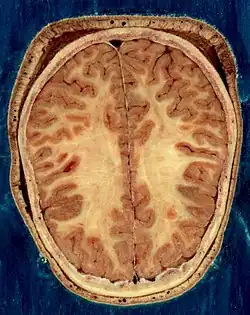

The cerebrum, brainstem, cerebellum, and spinal cord are covered by three membranes called meninges. The membranes are the tough dura mater; the middle arachnoid mater and the more delicate inner pia mater. Between the arachnoid mater and the pia mater is the subarachnoid space and subarachnoid cisterns, which contain the cerebrospinal fluid.[11] The outermost membrane of the cerebral cortex is the basement membrane of the pia mater called the glia limitans and is an important part of the blood–brain barrier.[12] In 2023 a fourth meningeal membrane has been proposed known as the subarachnoid lymphatic-like membrane.[13][14] The living brain is very soft, having a gel-like consistency similar to soft tofu.[15] The cortical layers of neurons constitute much of the cerebral grey matter, while the deeper subcortical regions of myelinated axons, make up the white matter.[7] The white matter of the brain makes up about half of the total brain volume.[16]

The outer part of the cerebrum is the cerebral cortex, made up of grey matter arranged in layers. It is 2 to 4 millimetres (0.079 to 0.157 in) thick, and deeply folded to give a convoluted appearance.[21] Beneath the cortex is the cerebral white matter. The largest part of the cerebral cortex is the neocortex, which has six neuronal layers. The rest of the cortex is of allocortex, which has three or four layers.[7]